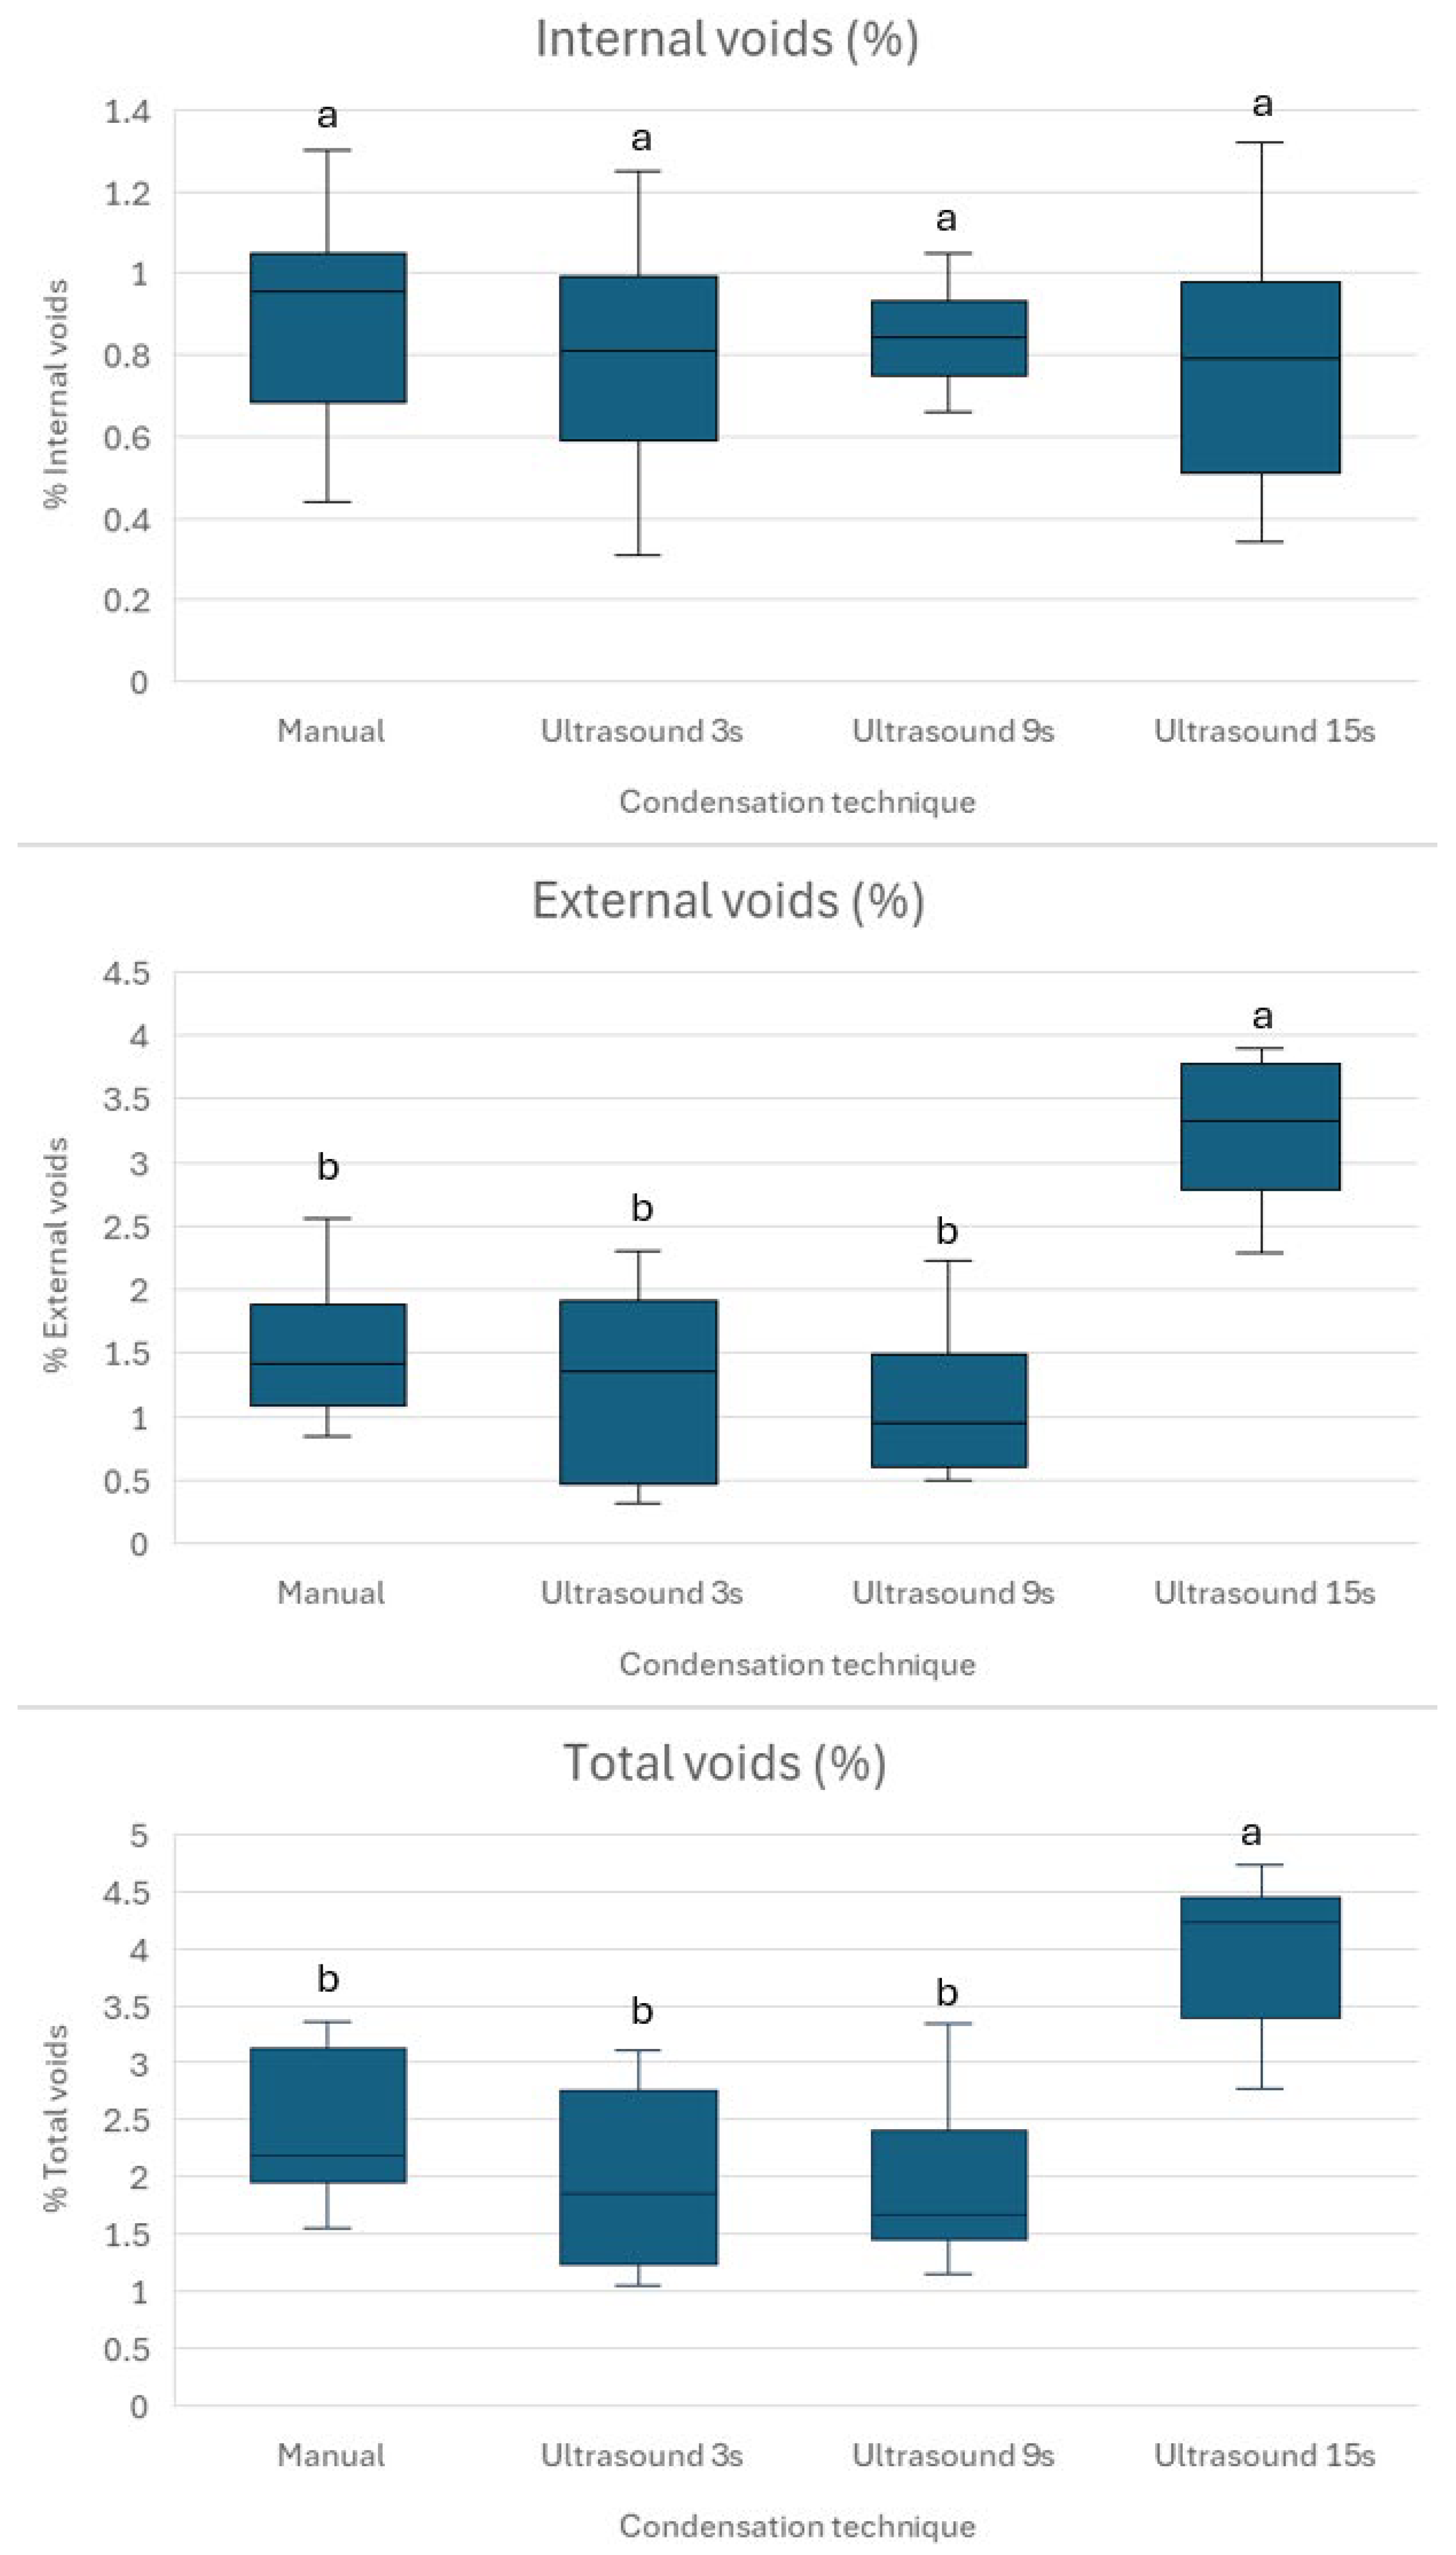

This study investigates the impact of varying durations of indirect ultrasonic activation on the quality of apical plugs formed with Well-Root™ PT, focusing on void formation and microhardness. The findings indicate that varying the duration of ultrasonic activation affects the quality of apical plugs made with premixed bioceramic putty. Specifically, it increases the percentage of external voids and decreases the microhardness while having no significant impact on the percentage of internal voids. Thus, the null hypothesis was partially rejected. The management of necrotic immature permanent teeth with open apices poses a significant challenge in endodontics due to the absence of an apical constriction, which complicates effective obturation and apical sealing [

13]. The consistent internal microstructure across all groups (

24]. Conversely, the lower void volumes and higher microhardness achieved with 3 s activation (

Figure 3 and

41]. This study shows that no placement technique is currently able to create void-free apical plugs (

Figure 2). Brief ultrasonic activation for 3 s minimizes void formation and maintains higher microhardness compared to longer durations of 9 and 15 s. Specifically, 15 s ultrasound condensation resulted in significantly higher external and total void volumes (

p < 0.001), suggesting that prolonged ultrasonic activation may disrupt the material’s homogeneity and its adaptation to dentin walls. This aligns with previous research, which reported that excessive ultrasonication (beyond 10 s) increases porosity and void formation in calcium silicate-based materials, such as mineral trioxide aggregate (MTA), due to over-vibration and potential microcavitation effects [

The absence of statistically significant differences in internal void volumes across groups (

p > 0.05) suggests that Well-Root™ PT, as a premixed bioceramic putty, produces comparable internal void volumes regardless of the condensation technique. This may be attributed to its injectable consistency and reduced technique sensitivity compared to MTA, which requires manual mixing and is more prone to voids when hand-condensed [

42]. The same study did not find any significant difference in void formation after ultrasonic activation. This may be attributed to the use of two-dimensional periapical radiograph, not used in the current study, which used more precise micro-CT assessment.

While the percentage void volumes reported in this study (1–5%) are relatively low, the size and distribution of voids are likely more critical to the mechanical strength of Well-Root™ PT apical plugs, as they can act as stress concentration points that compromise microhardness and fracture resistance [

Previous studies have reported similar findings for MTA, indicating that brief ultrasonic activation (2–8 s) enhances microhardness by improving material density [

36]. The high microhardness observed in Group 1 may reflect the stable, dense structure achieved through controlled manual condensation, even though this technique resulted in slightly higher void volumes compared to Group 2. The performance of Group 2, which utilized 3 s of ultrasonic activation, effectively balanced low void volumes with relatively high microhardness, indicating its potential as an optimal technique for Well-Root™ PT apical plugs.

Our findings on Well-Root™ PT’s void formation and microhardness can be contextualized by comparing them with those for MTA and Biodentine™, two widely used calcium silicate-based materials for apexification. Similarly to our results, studies on MTA show that brief ultrasonic activation (2–8 s) reduces void formation and enhances microhardness by improving material density, whereas prolonged activation (>10 s) increases porosity and reduces microhardness, aligning with the higher external voids and lower microhardness in our 15-s Ultrasonic group [

16,

36]. However, Well-Root™ PT’s premixed formulation exhibited consistent internal void volumes across all groups (

p > 0.05), unlike MTA, which is more prone to internal voids when manually mixed and condensed due to technique sensitivity [